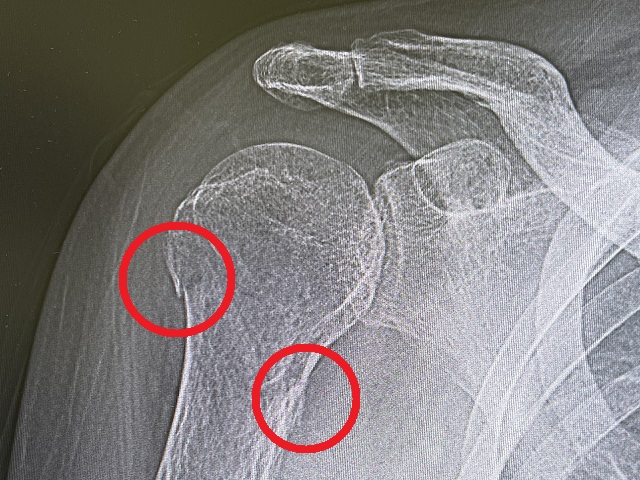

レントゲンを撮って、

「亀裂骨折ですね。しかも2箇所も。こいつはただ待つのみで、ほかにどうしようもありません。」

上腕亀裂骨折×2箇所